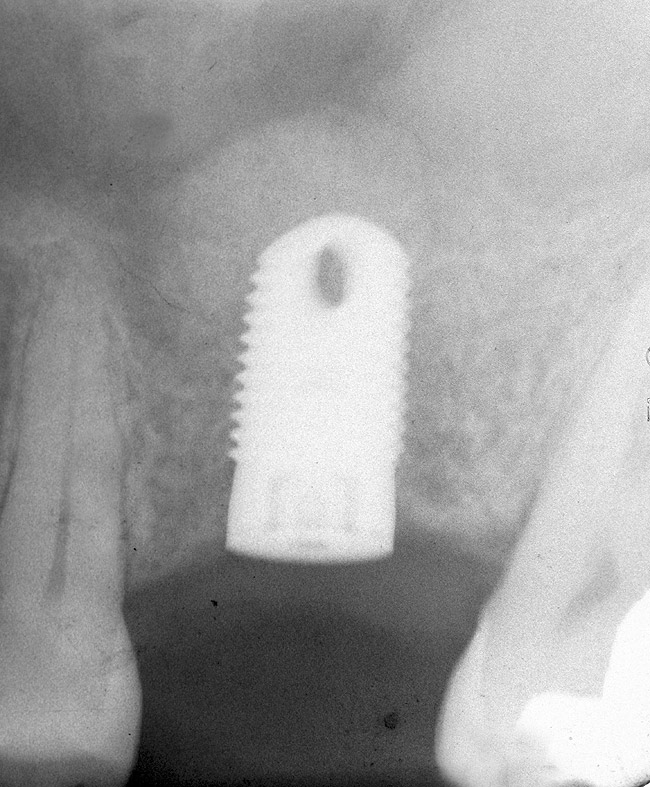

Figure 11  Insertion of a 4.8-mm implant, which fit snugly and increased the surface area for future osseointegration

Figure 11

Supracrestal Versus Subcrestal Implant Placement

In the posterior maxilla, the bone type is usually medium dense (Table 1). Therefore, if a paucity of subantral bone exists, it would be advantageous to retain as much cortical bone as possible after implant placement. Accordingly, thought should be given to keeping the implant platform surpracrestally (Figure 11). Positioning the implant platform coronal to the crest of bone facilitates formation of a supracrestal biologic width with less bone loss. In contrast, placement of the implant platform crestally or subcrestally will result in bone loss and development of a subcrestal biologic width.36